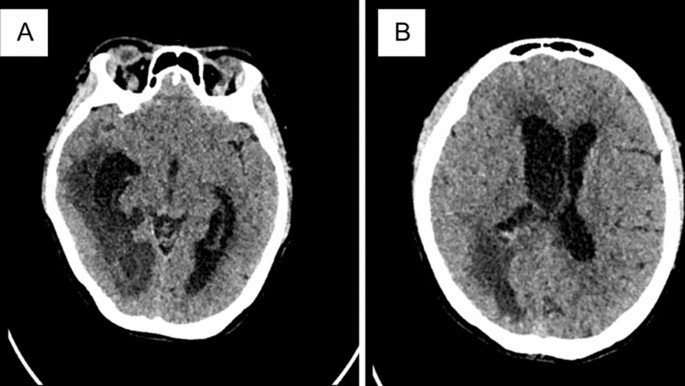

On day 5 in the ICU, the patient’s condition worsened; her level of consciousness deteriorated (Glasgow coma scale E3M5V2), and she had sudden apnea. Obstetric Doppler ultrasonography revealed cerebral blood-flow redistribution of the fetus. Head computed tomography (CT) scan revealed diffuse brain swelling and hydrocephalus (Fig. 1). The patient was then intubated, and scheduled for an emergency cesarean section to terminate the pregnancy. The baby was born alive at 31 weeks. External ventricular drainage (EVD) was also inserted to alleviate the hydrocephalus; 2 days following the caesarean delivery, the patient’s condition improved and she was already extubated. The patient’s condition continued to improve and she was discharged to the ward on day 13 of care.

First patient’s head computed tomography: A ventriculitis and communicans hydrocephalus. B subfalcine herniation to the left